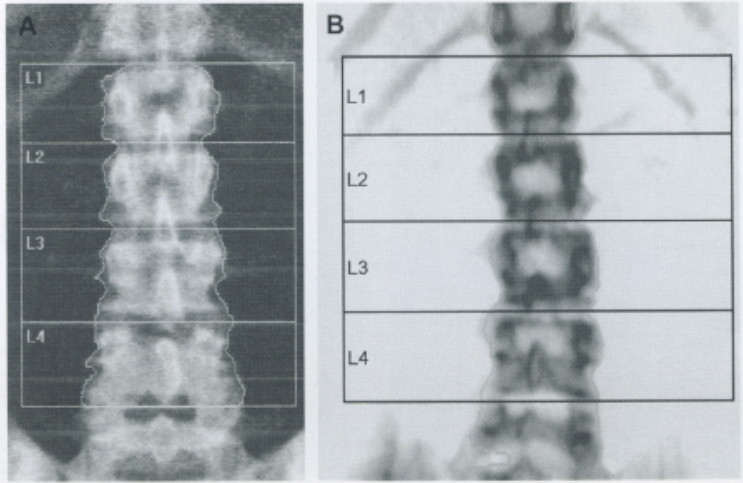

Scansione della colonna lombare (L1-L4)

Il paziente deve essere posizionato supino con i femori flessi a 90 gradi su un apposito cubo di gommapiuma per ridurre la lordosi lombare e appiattire la colonna sul tavolo di scansione.19

L’immagine acquisita deve essere centrata, con la colonna parallela ai bordi e deve includere la parte superiore delle creste iliache e l’ultima coppia di coste (T12) come punti di riferimento anatomico.20 Un’analisi corretta richiede l’inclusione di almeno due vertebre contigue.

Una vertebra deve essere esclusa se è presente una frattura, un’alterazione strutturale grossolana (come un emangioma o esiti chirurgici) o se il suo T-score differisce di oltre 1.0 DS rispetto alle vertebre adiacenti.